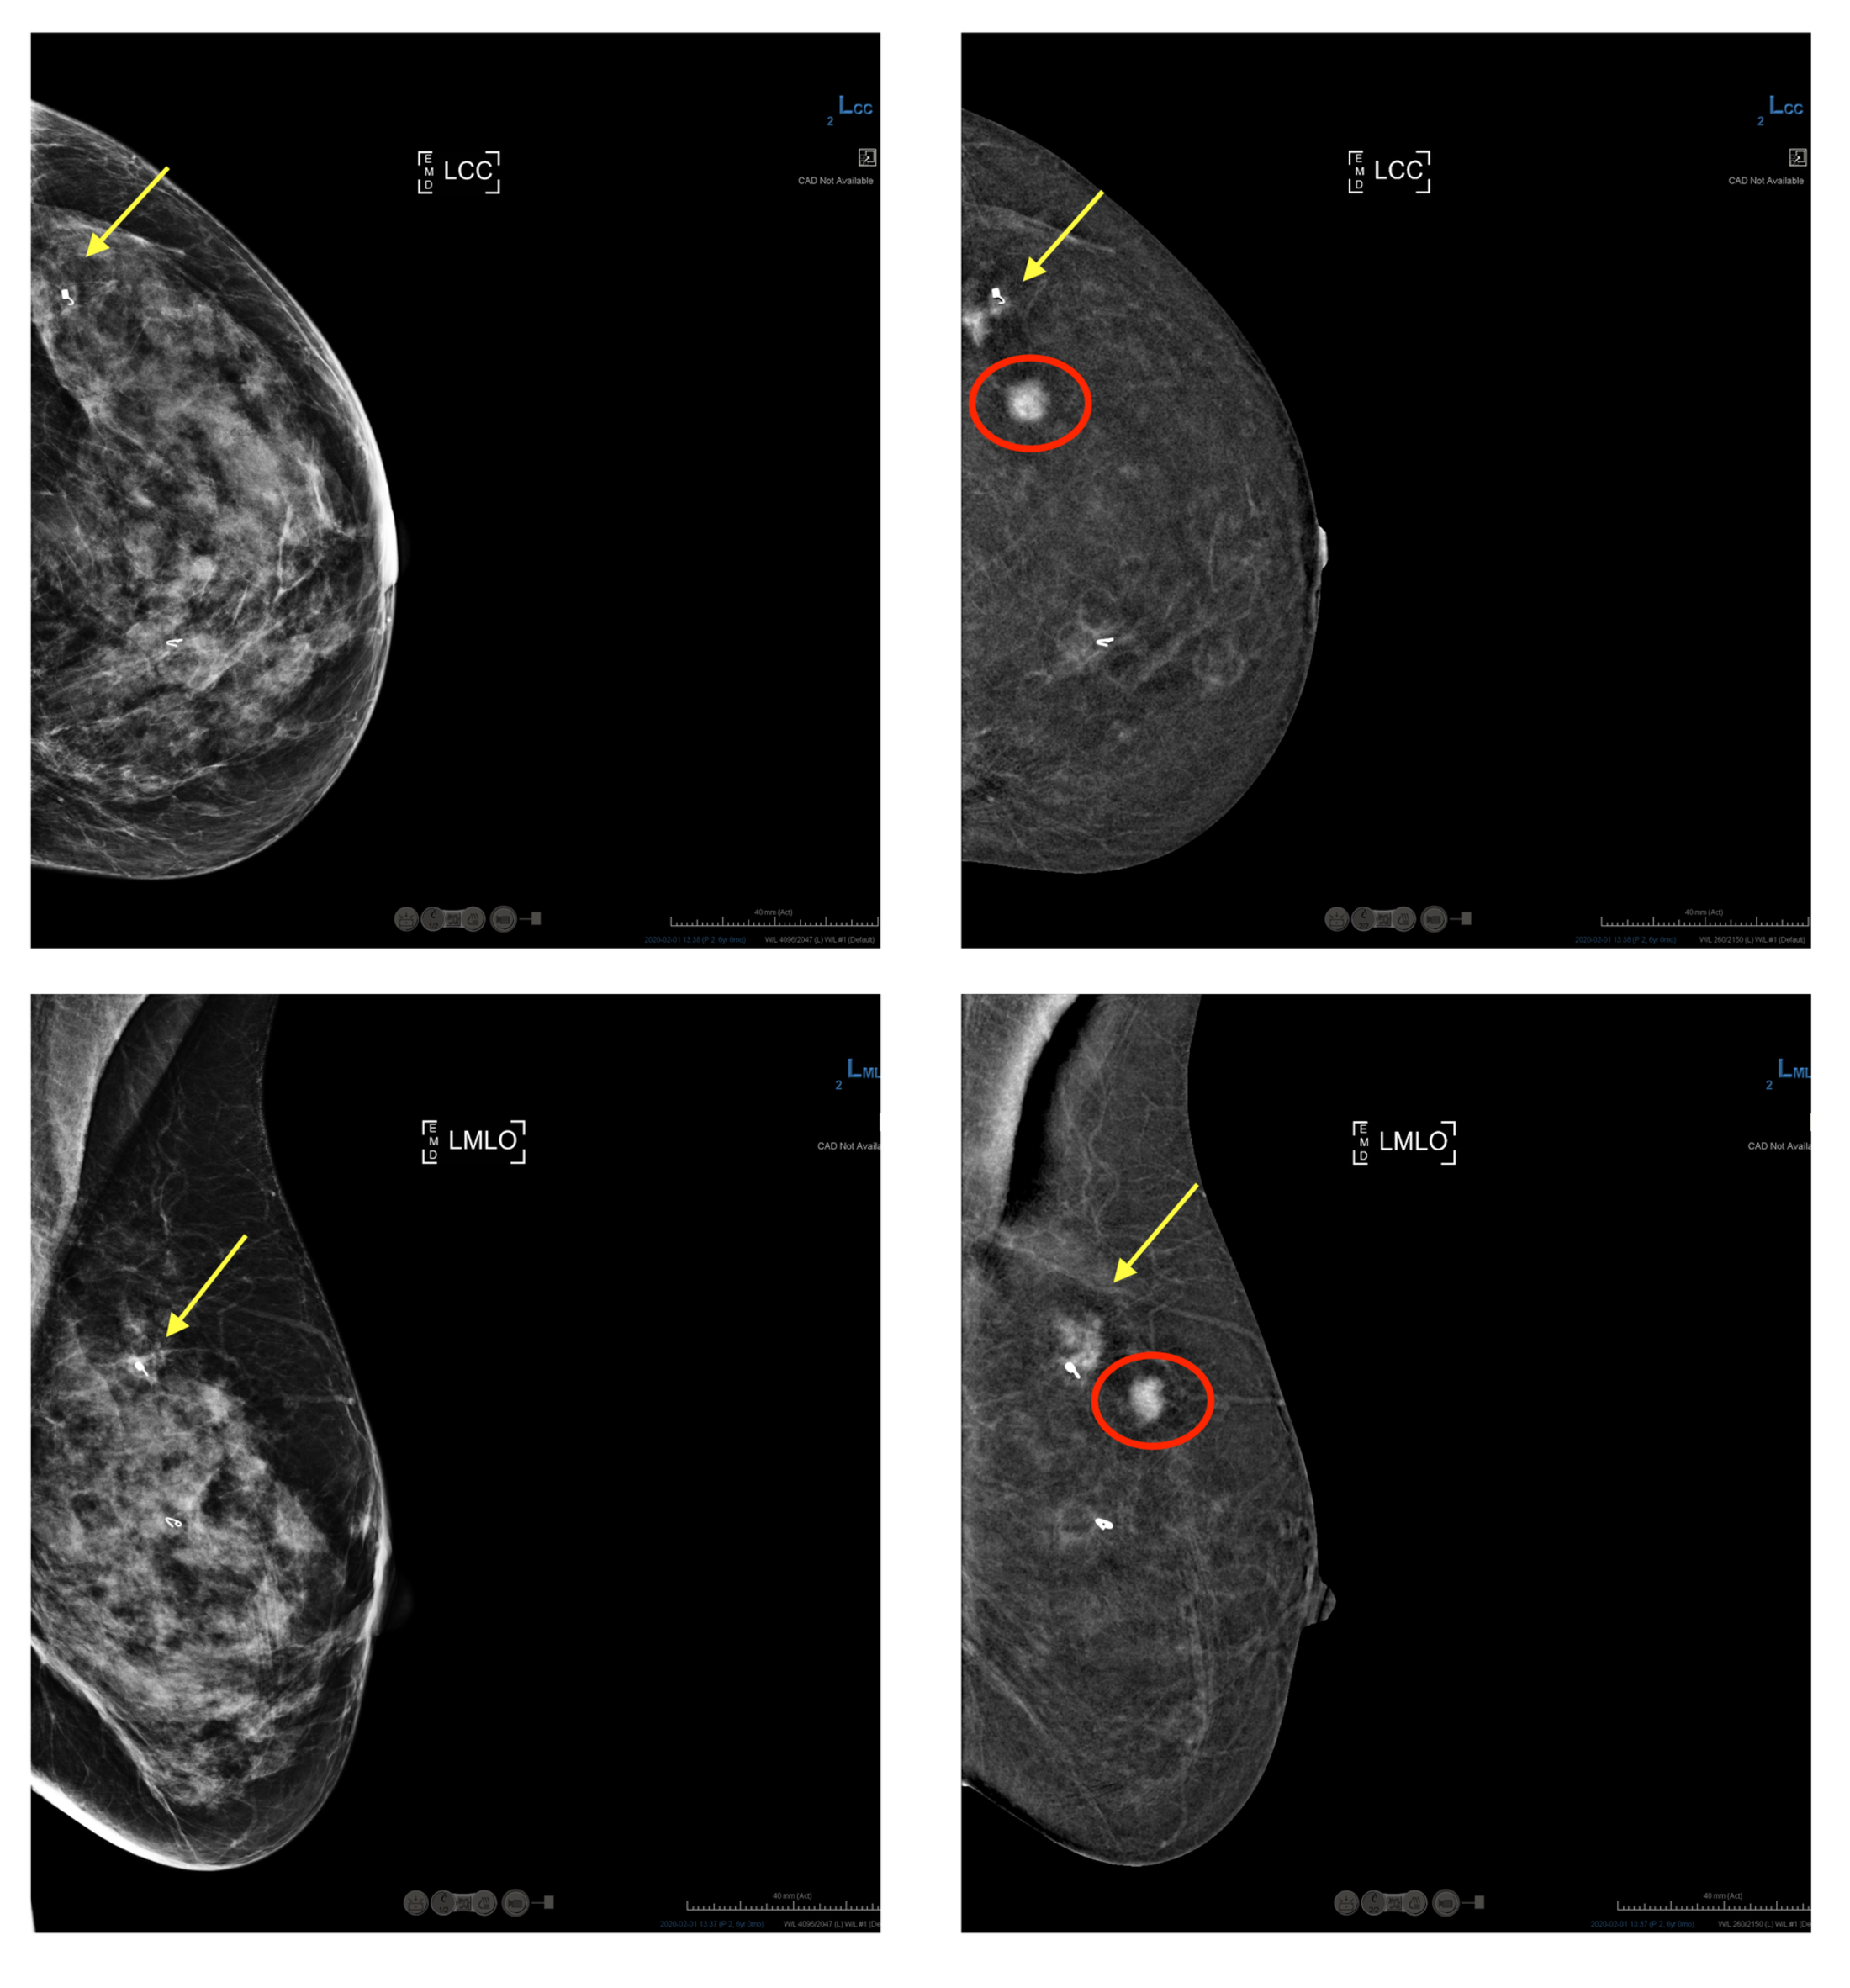

Scans showing what is visible via traditional mammogram versus contrast-enhanced mammogram.

In these images from Hologic, a patient presented for a screening mammogram (left images). The exam revealed an area of concern (yellow arrow) which was subsequently biopsied and found to be a cancer. Contrast-enhanced mammography was performed (right images) and revealed an additional mass (red circle). A biopsy was performed and confirmed the mass to also be cancer. Images courtesy of HOLOGIC, Inc. and affiliates.